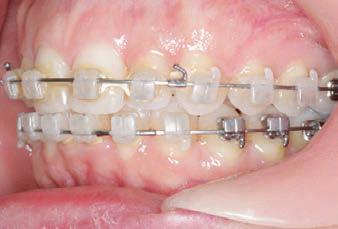

Carriere Motion 3D Appliance

Fastrack your orthodontic treatments. Save 6 months or more.

The SAGITTAL FIRST™ Philosophy is a time-tested approach that standardises, simplifies, and shortens Class II and Class III treatment times. It employs the Carriere Motion 3D Appliance to treat the AP dimension at the beginning of treatment before placing brackets or aligners. By resolving the most difficult part of treatment first, you can achieve a Class I platform in 3 to 6 months, shortening total treatment time by a minimum of 6 months1. You know how excited patients and parents become when you mention shorter treatment times.

CLASS II DIV.1 - Marra

PROVIDED BY: DR. LUIS CARRIÈRE

INITIAL - 4/4/18

PROGRESS 1 - 26/9/18 - Class I platform accomplished in 5.75 months with Motion 3D COLOR Appliance

PROGRESS 2 - 26/9/18 - Placement of the SLX 3D Clear Brackets

[CONTINUED ON NEXT PAGE]

with M-ONE .015 Cu Nitanium 27°

PROVIDED BY: DR. LUIS

PROGRESS 3 - 30/10/18 - With M-TWO .020 x .020 Cu Nitanium 35° archwire

PROGRESS 4 - 27/11/18 - 3 links power chain: 5, 4, bypass 3 to crimp hooks

PROGRESS 5 - 13/3/19 - With M-TWO .020 x .020 Cu Nitanium 35° archwire

PROGRESS 6 - 1/8/19 - With M-THREE.019 x .025 Beta Titanium wire

52 HENRY SCHEIN ORTHODONTICS

FINAL - 10/10/19 - Appliances removed AFTER

PROGRESS 7 - 10/10/19 - Final day in SLX 3D Clear Brackets BEFORE